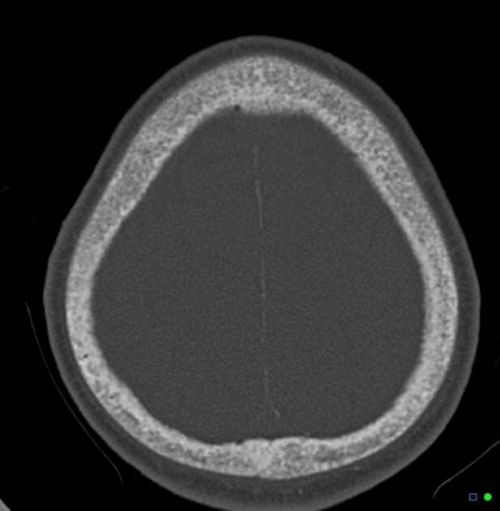

Hyperparathyroidism, a condition of excessive parathyroid hormone (PTH) secretion, can occur at any age and affects both men and women, although it is more common in postmenopausal women [1]. Primary hyperparathyroidism refers to inappropriate, excessive PTH secretion originating from the parathyroid glands themselves, leading to hypercalcemia (high blood calcium) [1, 2].

Untreated primary hyperparathyroidism increases the risk of complications related to chronic hypercalcemia and excessive PTH action, including osteoporosis (due to increased bone resorption), nephrolithiasis (kidney stones), nephrocalcinosis, bone pain, fractures, and potentially non-specific symptoms like fatigue, depression, constipation, and cognitive difficulties ("stones, bones, abdominal groans, thrones, and psychiatric overtones") [1, 2].

Tertiary hyperparathyroidism develops when the parathyroid glands, after prolonged stimulation in secondary hyperparathyroidism (usually due to end-stage renal disease), become autonomous and continue to oversecrete PTH even after the underlying cause of hypocalcemia is corrected (e.g., after successful kidney transplantation) [1, 2]. This results in hypercalcemia along with persistently elevated PTH levels [1, 2]. The glands are typically markedly hyperplastic, and sometimes an adenoma may develop within a hyperplastic gland [1].